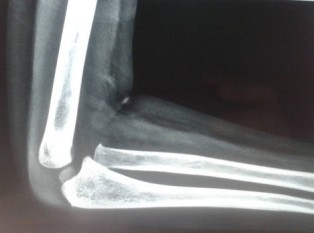

Long bone fractures of children have a very good potential of remodelling. However there are certain criteria which determine the degree of remodelling that takes place. In general, younger children have greater potential of remodelling. Fractures close to joint also have greater potential to remodel. Malunion in the direction of joint axis is better tolerated by patient than rotational malalignment. It is better that fractures are fixed correctly at the time of injury. Reading radiographs of children is difficult and hence a specialist is required.They can be treated with plaster or with nailing and plating. Below are three examples of fracture which were malunited and hence needed to be operated again.

Malunited fractures, in which the bones mend in an incorrect position following a fracture, are the specialty of Dr. Sameer Desai, a top Pediatric Orthopedic Surgeon in Pune. He uses advanced corrective techniques to ensure proper alignment, function, and mobility in children. For expert Malunited Fracture care in Pune, contact Dr. Sameer Desai right now!